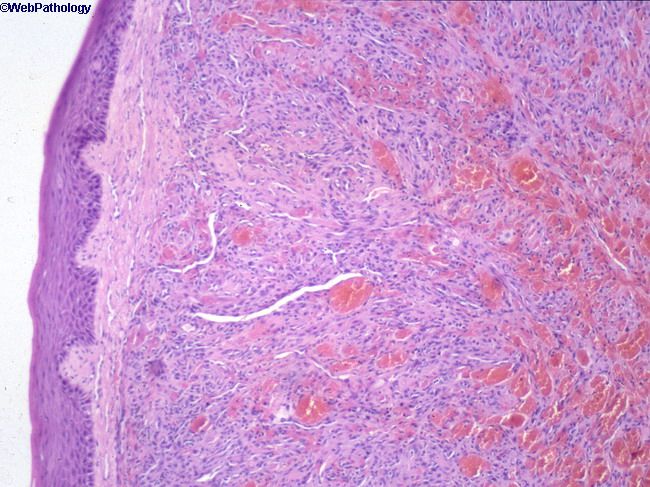

Саркома Капоши На Коже Фото

Саркома Капоши На Коже Фото 115 фотографий